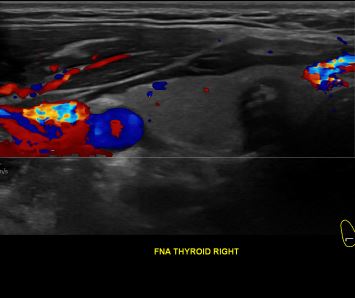

상기환자 외부건진 이상소견으로 내원하신 40대 중반 남성분으로

의심스러운 갑상선 우엽 세포검사후 갑상선암으로 진단되었습니다